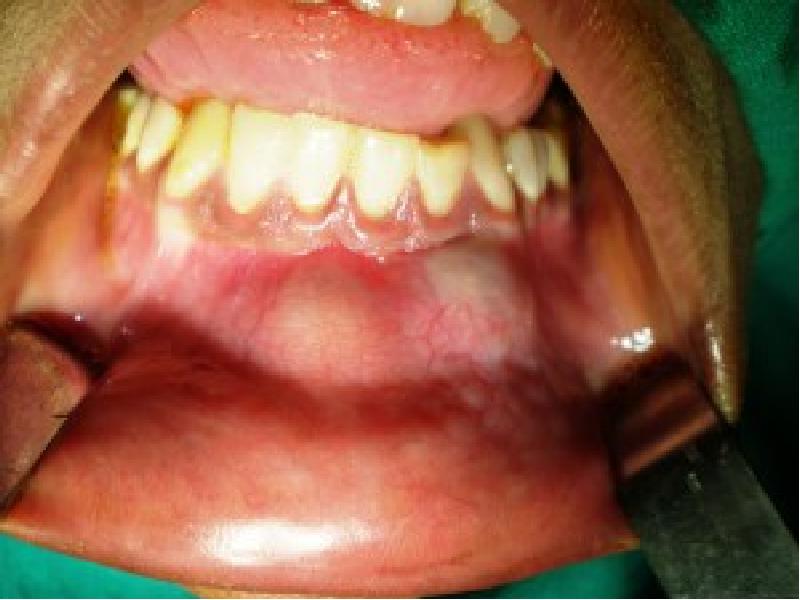

- 54. Киста прорезывания Разновидность фолликулярной кисты (фолликулярная киста, связанная с коронкой прорезывающегося